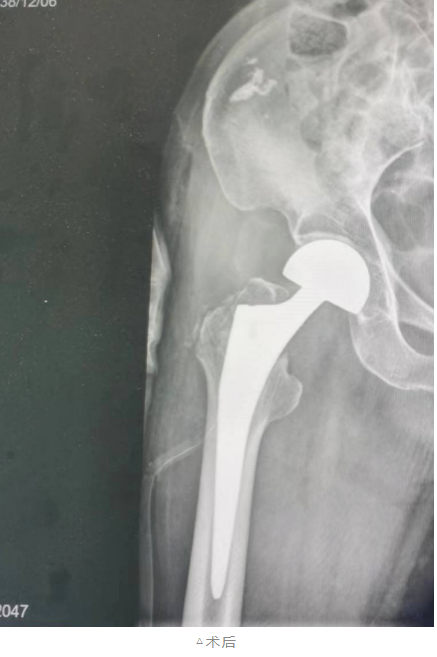

患者家属同意手术方案后,经过充分的术前准备,骨科团队医生们选择前侧入路进行髋关节置换,切口仅有一根手指长度,从肌间隙进入,只需离断一根动脉分支,不会损伤肌肉。

手术十分顺利,患者术中出血量很少,术后6小时在护士的指导下进行功能锻炼,术后第一天便能下床走动。张奶奶一家向医护人员竖起了大拇指,连声感谢医护人员的精湛技术。

首例髋关节置换微创DAA入路技术的成功完成,

填补了全县的一项技术空白,

标志着我院骨科医疗技术水平迈上新台阶。